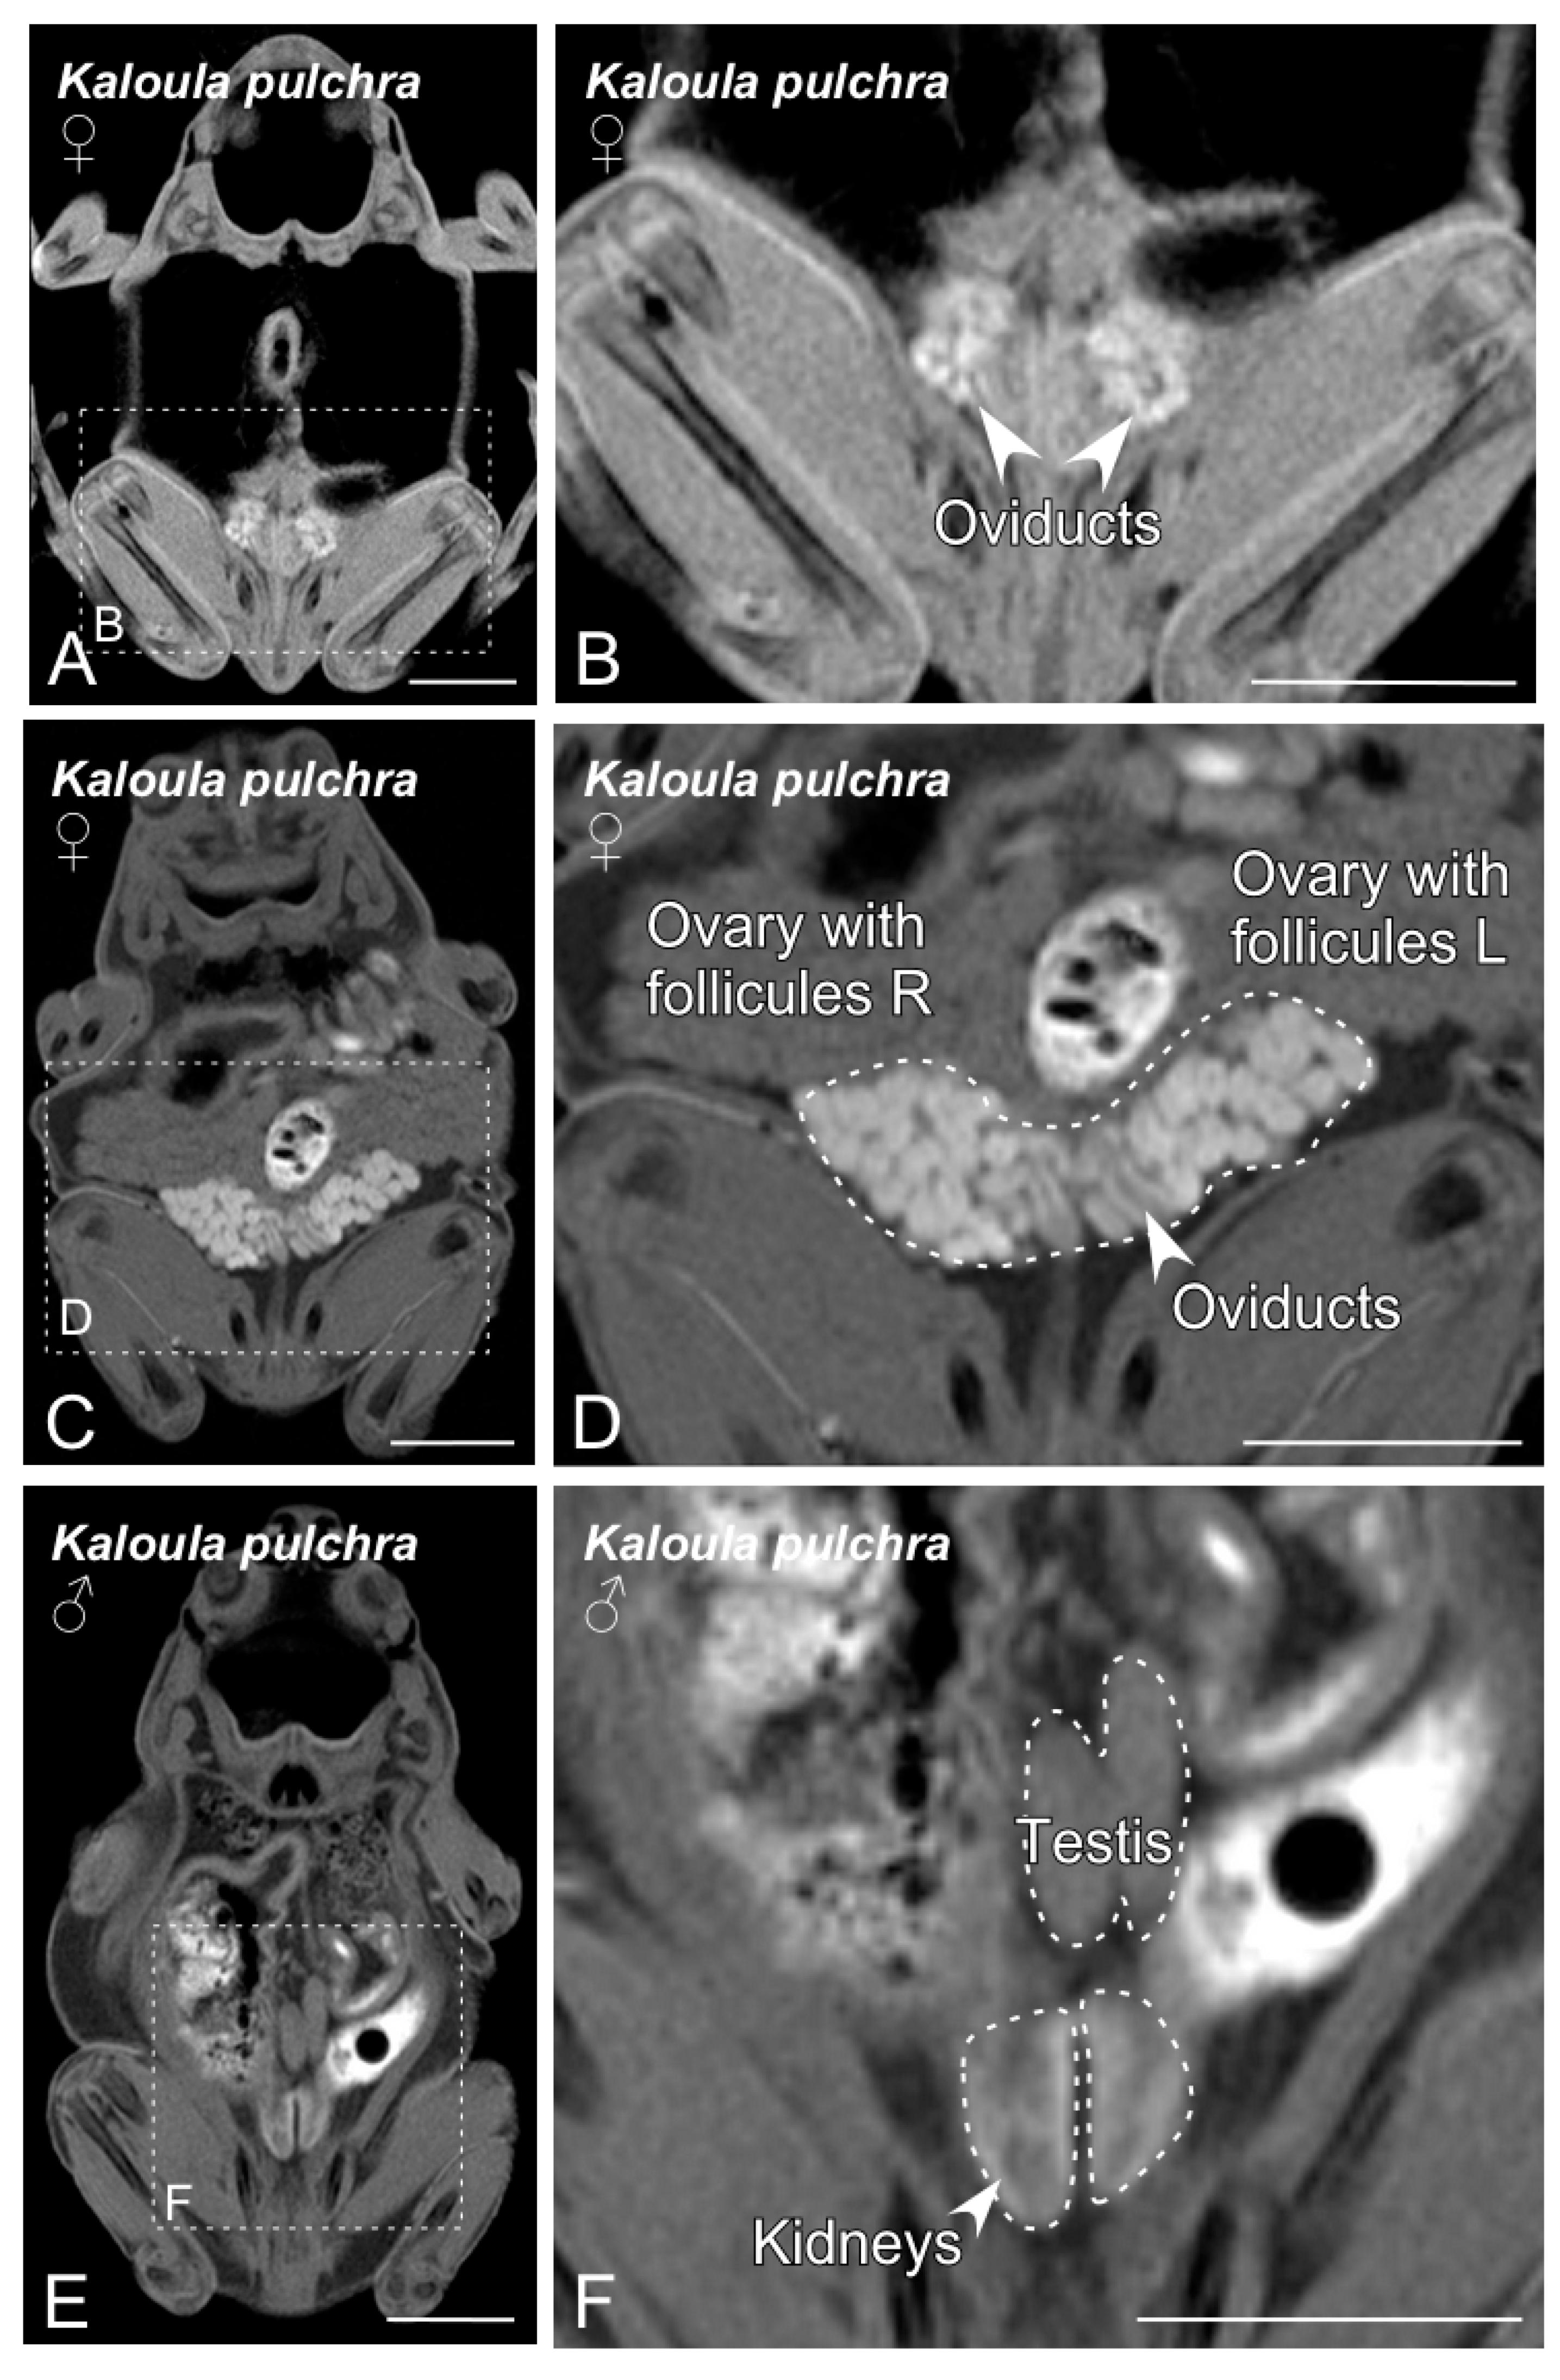

Figure 2. Magnetic resonance imaging (MRI) slices selected to classify Kaloula pulchra anurans by sex. Images from (A) to (D) show the main sexual structures identified in a non-gravid (A,B) and gravid (C,D) Kaloula pulchra female. Images (E) and (F) show testis and kidneys in a Kaloula pulchra male. The dashed lines in (A,C,E) indicate the magnification photos showed in (B,D,F). Scale bars = 1 cm. |